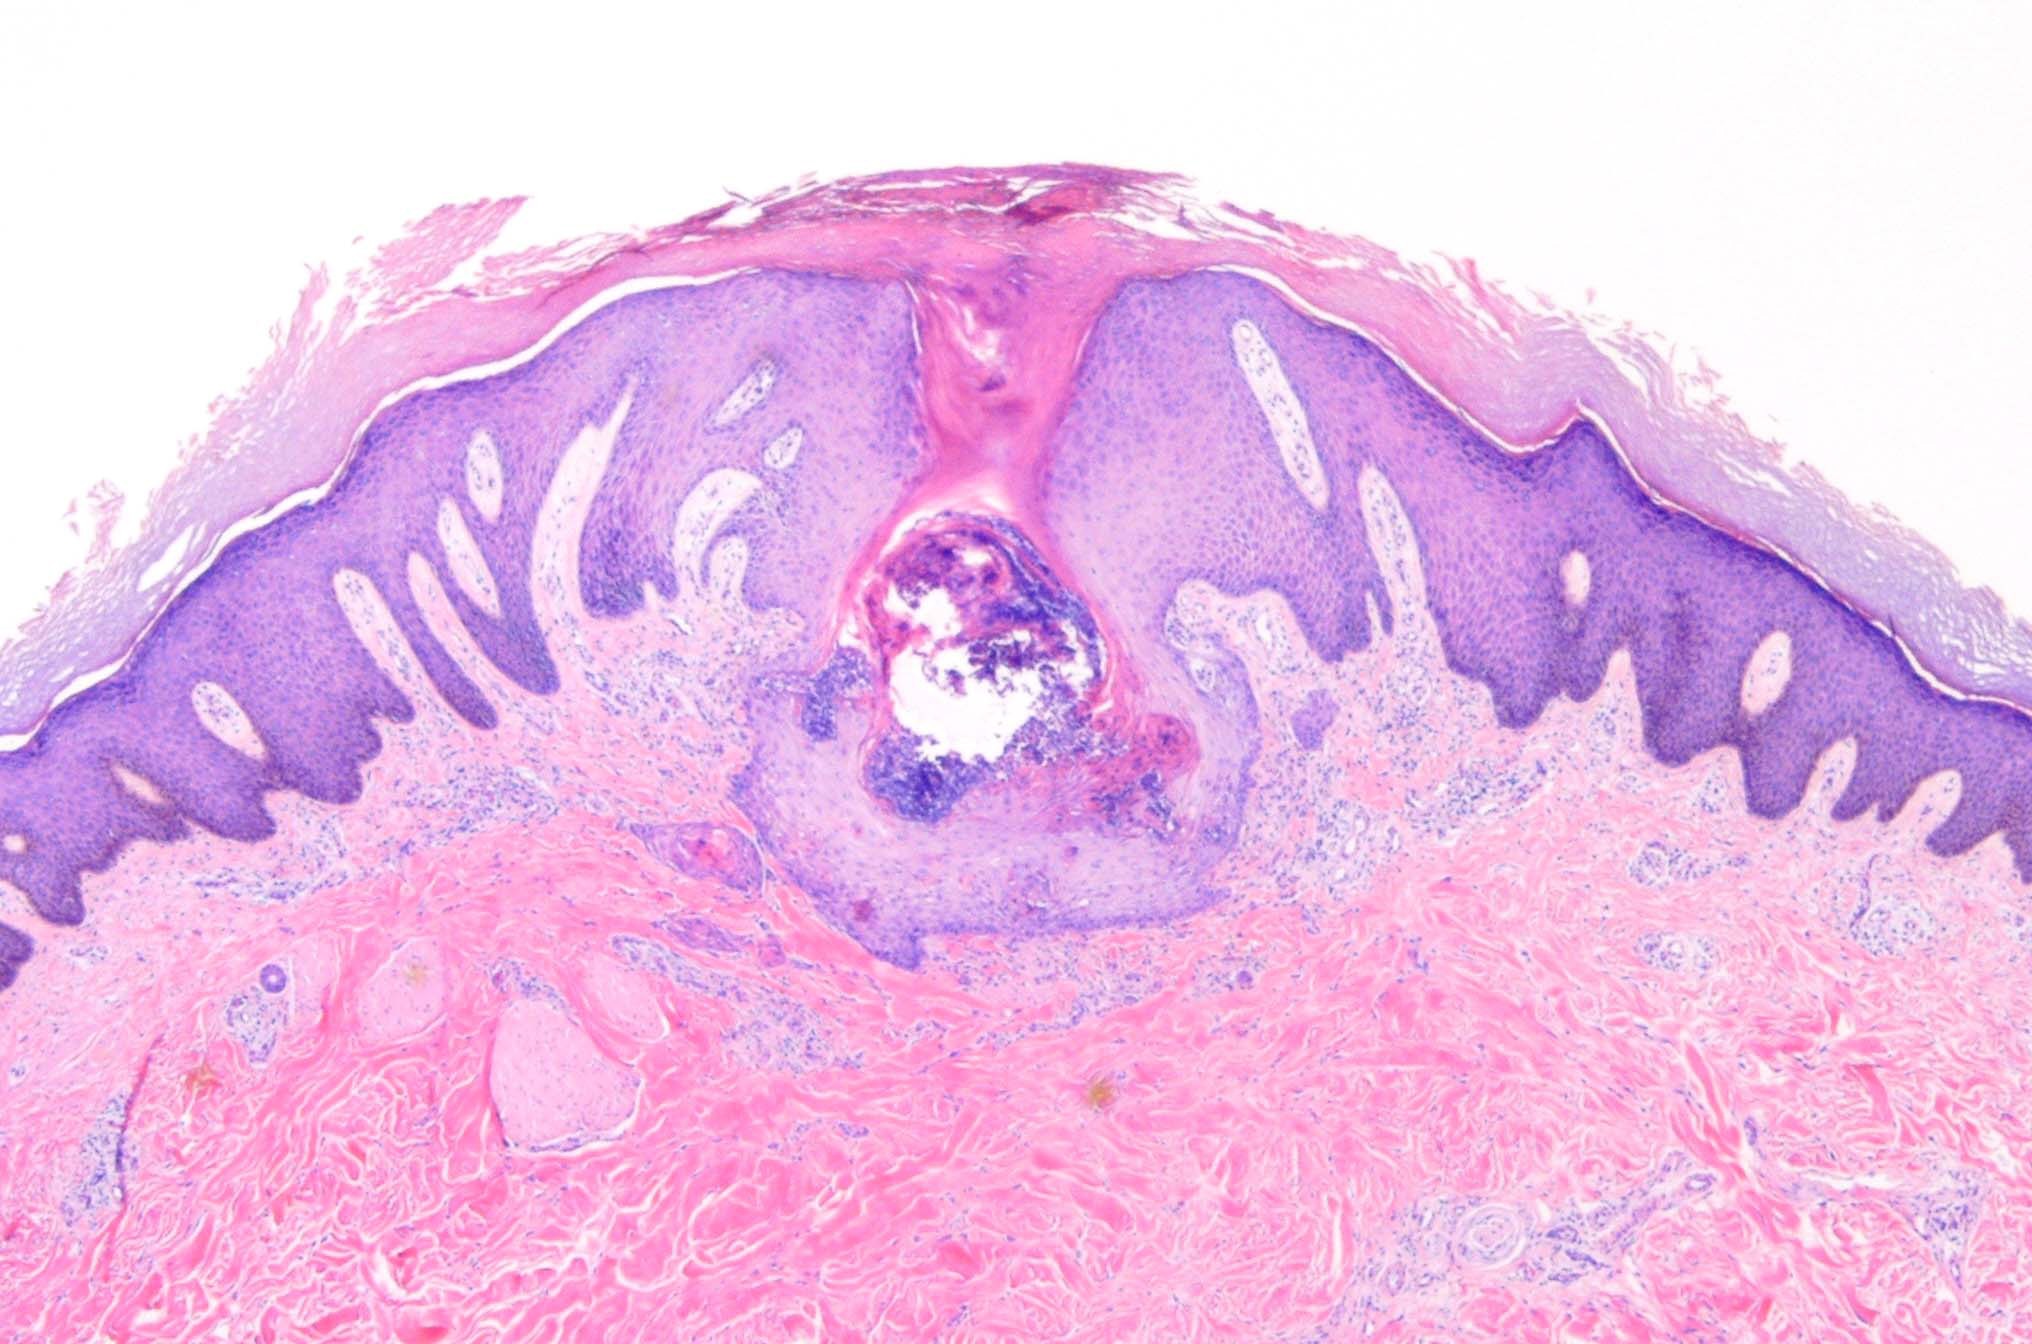

Acquired perforating dermatosis = الجلاد الثاقب المكتسب